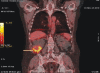

Urinary tract infection (UTI) is the most common infection contracted by renal allograft recipients. In patients of autosomal dominant polycystic kidney disease (ADPKD), cyst infection presents a complex diagnostic and therapeutic challenge especially in the post transplant period. Accurate diagnosis forms the cornerstone in salvaging the graft from potentially catastrophic outcome. We describe a case of xanthogranulomatous pyelonephritis (XPN) in the native kidney in a patient of post transplant ADPKD which presented as frequently relapsing UTI with graft dysfunction where in accurate diagnosis was made possible with the aid of 18-fluorodeoxyglucose (FDG) - Positron emission computerized tomography (PET/CT).